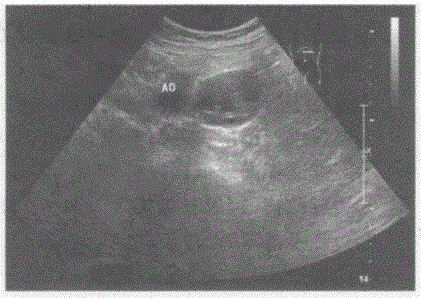

问题 临床资料:男,73岁,自述2年前体检发现左侧腹膜后肿物,大小4.3cm×3.0cm,此后多次复查肿物大小无明显变化。 超声综合描述:左肾下极与腹主动脉之间可见不均质低回声,与腹主动脉关系密切,边界清晰,形态规则,内可见形态不规则无回声,CDFI:其内及周边均未见动静脉血流信号。见下图及彩图55。 {图2} {图3} 超声提示:

选项 A.腹膜后囊实性占位(神经鞘瘤) B.腹腔囊实性占位 C.左肾囊实性占位 D.左肾上腺囊实性占位(嗜铬细胞瘤)

答案 A